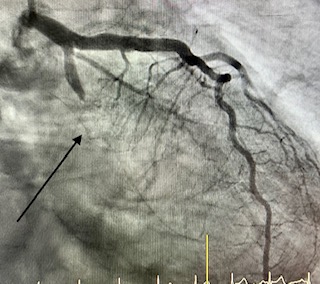

Angioplàstia amb stent

L'angioplàstia coronària transluminal percutània amb implantació de stent ha estat capaç, a les sales de RX dels laboratoris d'Hemodinàmica i Cardiologia Intervencionista, de combatre eficaçment a la malaltia que més mortalitat causa en les societats modernes: la malaltia coronària.

Angioplàstia amb stent en un infart (artèria tancada 100%)